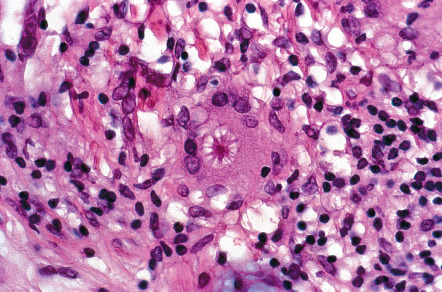

The histopathologic hallmark of sarcoidosis is the presence of superficial and deep dermal epithelioid cell granulomas devoid of prominent infiltrates of lymphocytes or plasma cells (“naked tubercles”) ( Fig. 93.6 ). Central caseation is usually absent, although fibrinoid deposition may be observed in up to 10% of cases. Multinucleated histiocytes (“giant cells”) are usually of the Langhans type, with nuclei arranged in a peripheral arc or circular fashion. The giant cells may contain eosinophilic stellate inclusions known as asteroid bodies ( Fig. 93.7 ) or rounded laminated basophilic inclusions known as Schaumann bodies, although neither is specific or required for the diagnosis. Asteroid bodies represent engulfed collagen, whereas Schaumann bodies likely represent degenerating lysosomes. Notably, up to 20% of biopsies of sarcoidosis contain polarizable material; therefore its presence does not exclude the diagnosis. In vulvar sarcoidosis, transepidermal elimination of the granulomas may be seen.

A range exists within the histologic spectrum of sarcoidosis, from the characteristic tubercles with minimal or no surrounding lymphocytic inflammation to unusual cases with dense lymphocytic and plasmacytic infiltrates around and within the nodular histiocytic aggregates. Occasionally, these aggregates may extend into the subcutaneous fat, producing the clinical features of Darier–Roussy sarcoidosis.